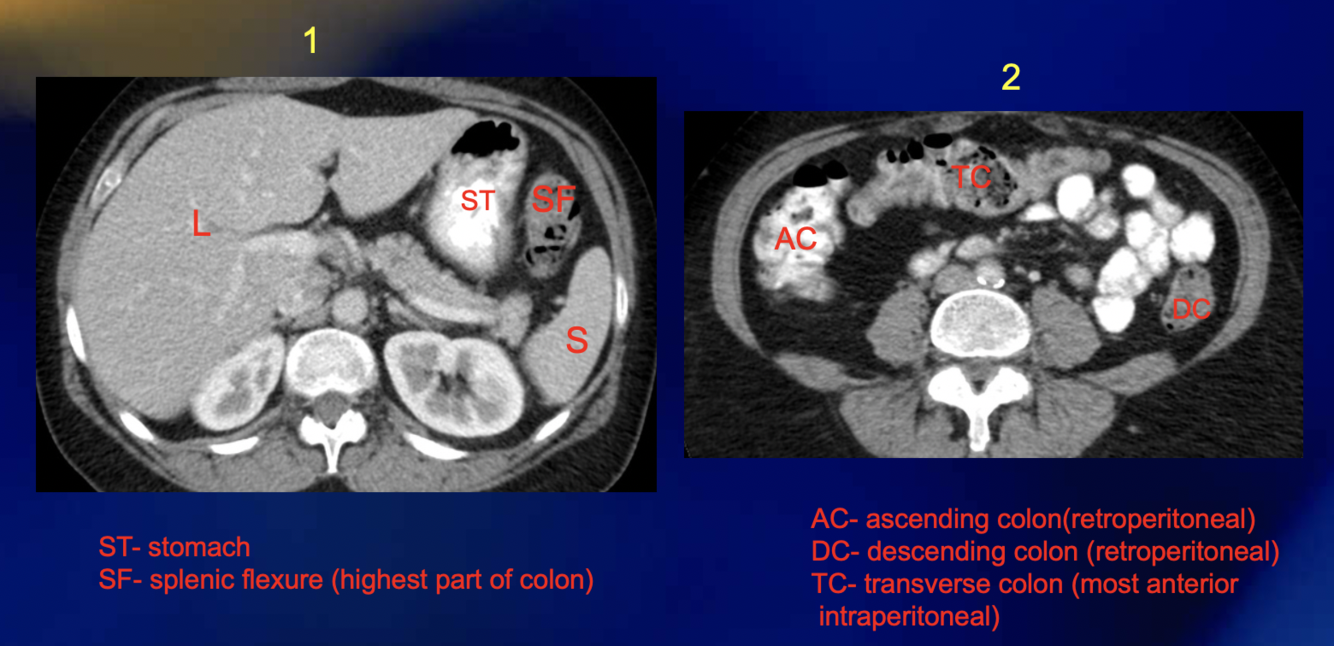

What is seen on the ascending colon?